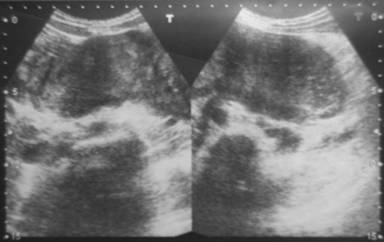

A 24-year-old woman with a history of mild epigastric pain radiating to the back and chronic constipation for the last two years was admitted to hospital for further investigation. Physical examination revealed a palpable large epigastric mass. Her medical and family history including malignancy or inherited disease was unremarkable. Laboratory investigations showed a normal hemogram; white blood cell 6,400 mm-3 (reference range: 4,500-11,000 mm-3), hemoglobin concentration 14.2 g/dL (reference range: 12-16 g/dL), hematocrit 43.7% (reference range: 35-47%) and platelet 243,000 mm-3 (reference range: 130,000-400,000 mm-3). Biochemical tests including kidney and liver function tests were within normal limits. Abdominal ultrasonography showed a hypoechoic solid mass, 13x5 cm in cross diameter, located at the epigastric region (Figure 1). Computed tomography imaging of the abdomen confirmed a solitary mass in epigastric region that begins from posterior of stomach, fills little curvature and extends to pelvis, invades vascular structures by encircling them and extends to retroperitoneal regions that was considered as it may have mesenchymal origin. The patient underwent a tumor excision.

Figure 1. Abdominal ultrasonography showed a hypoechoic solid mass. |